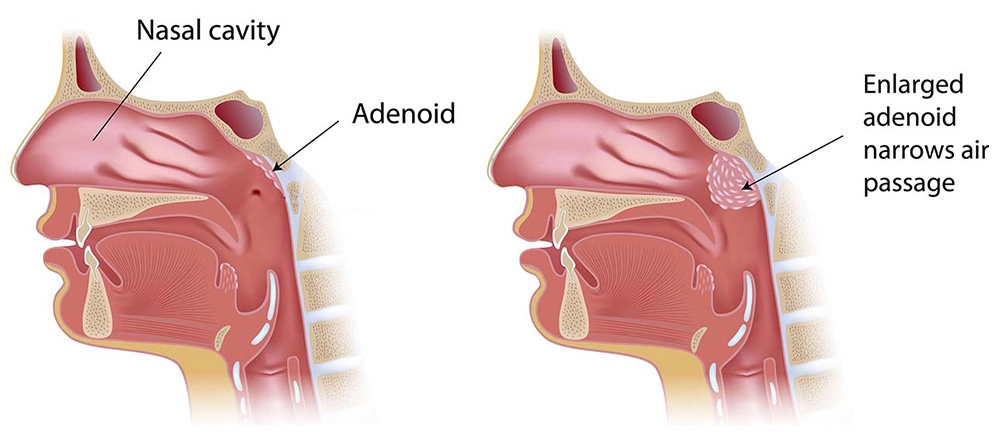

Adenoidectomy is the surgical removal of the adenoids—small lymphatic tissue located behind the nasal passage. When these become enlarged or infected frequently, they can block airways, cause snoring, breathing problems, and persistent ear or sinus infections.

- Enlarged adenoids

- Breathing difficulty during sleep

- Nasal blockage or speech issues